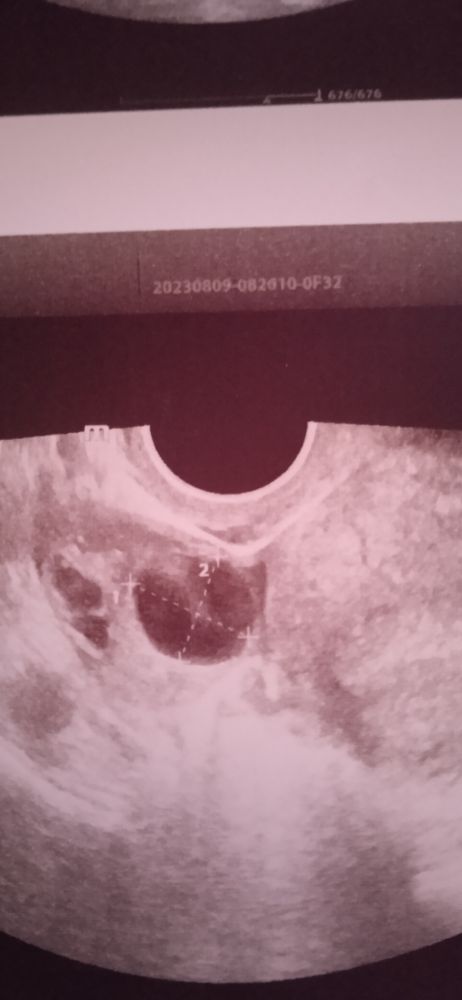

Девочки, подскажите, это овуляция? Вчера сильные боли в районе яичника, пошла на УЗИ, а врач не знает что это.

У вас киста в правом яичнике, она может давать боль и сильную, сама намучалась с ними

Екатерина , она написала киста, сказала, что фолликул. Два дня назад был фолликул 14*15, правда в другом месте делала. На вопрос это овуляция, узистка сказала, я не знаю, может у тебя всегда жидкость. Нет у меня всегда там жидкости, позавчера точно. Боли были два часа, потом пропали и больше нет их. После УЗИ больше вопросов, чем ответов. Первый доминант появился за долгое время.